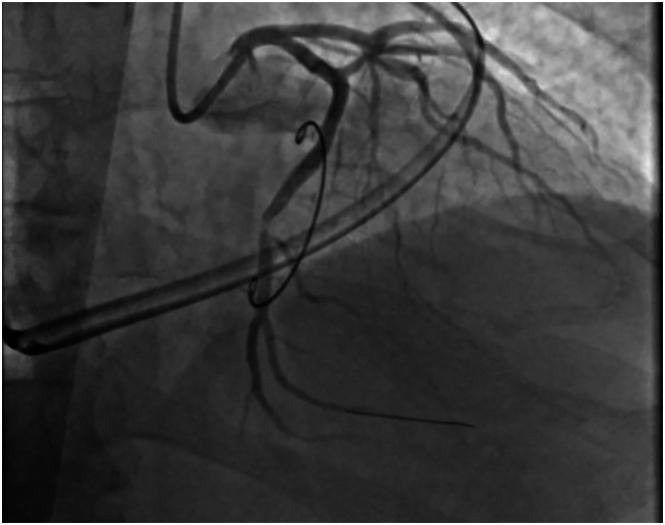

We describe a rare but interesting complication of totally endoscopic robotic mitral valve repair in a patient with severe mitral regurgitation. The mitral valve was repaired robotically by standard techniques, and the intraoperative transesophageal echocardiogram demonstrated no residual mitral regurgitation. However, there was unexpected hypokinesia of the posterior and lateral walls of the left ventricle, with subsequent electrocardiography showing acute ST elevations of the lateral segment. Immediate cardiac catheterization revealed occlusion of the left circumflex artery. Aspiration thrombectomy was performed and a drug-eluting stent placed to restore the contour, thus preventing potential morbidity of the patient.

我们描述了一例严重二尖瓣反流患者在完全内镜机器人二尖瓣修复术中出现的罕见但有趣的并发症。采用标准技术通过机器人对二尖瓣进行修复,术中经食管超声心动图显示无残余二尖瓣反流。然而,左心室后壁和侧壁出现意外的运动减退,随后心电图显示侧壁导联急性ST段抬高。立即进行心脏导管检查发现左旋支动脉闭塞。实施了抽吸血栓切除术并置入药物洗脱支架以恢复血管形态,从而预防患者可能出现的并发症。